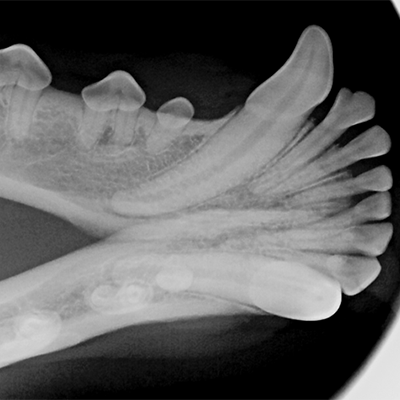

• Fogászati RTG digitális  iM3 technikával